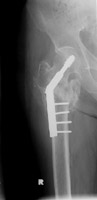

- Click on the image for a larger versionEAP radiograph of the right hip. The preceding fracture has undergone fixation with a dynamic hip screw and side plate.